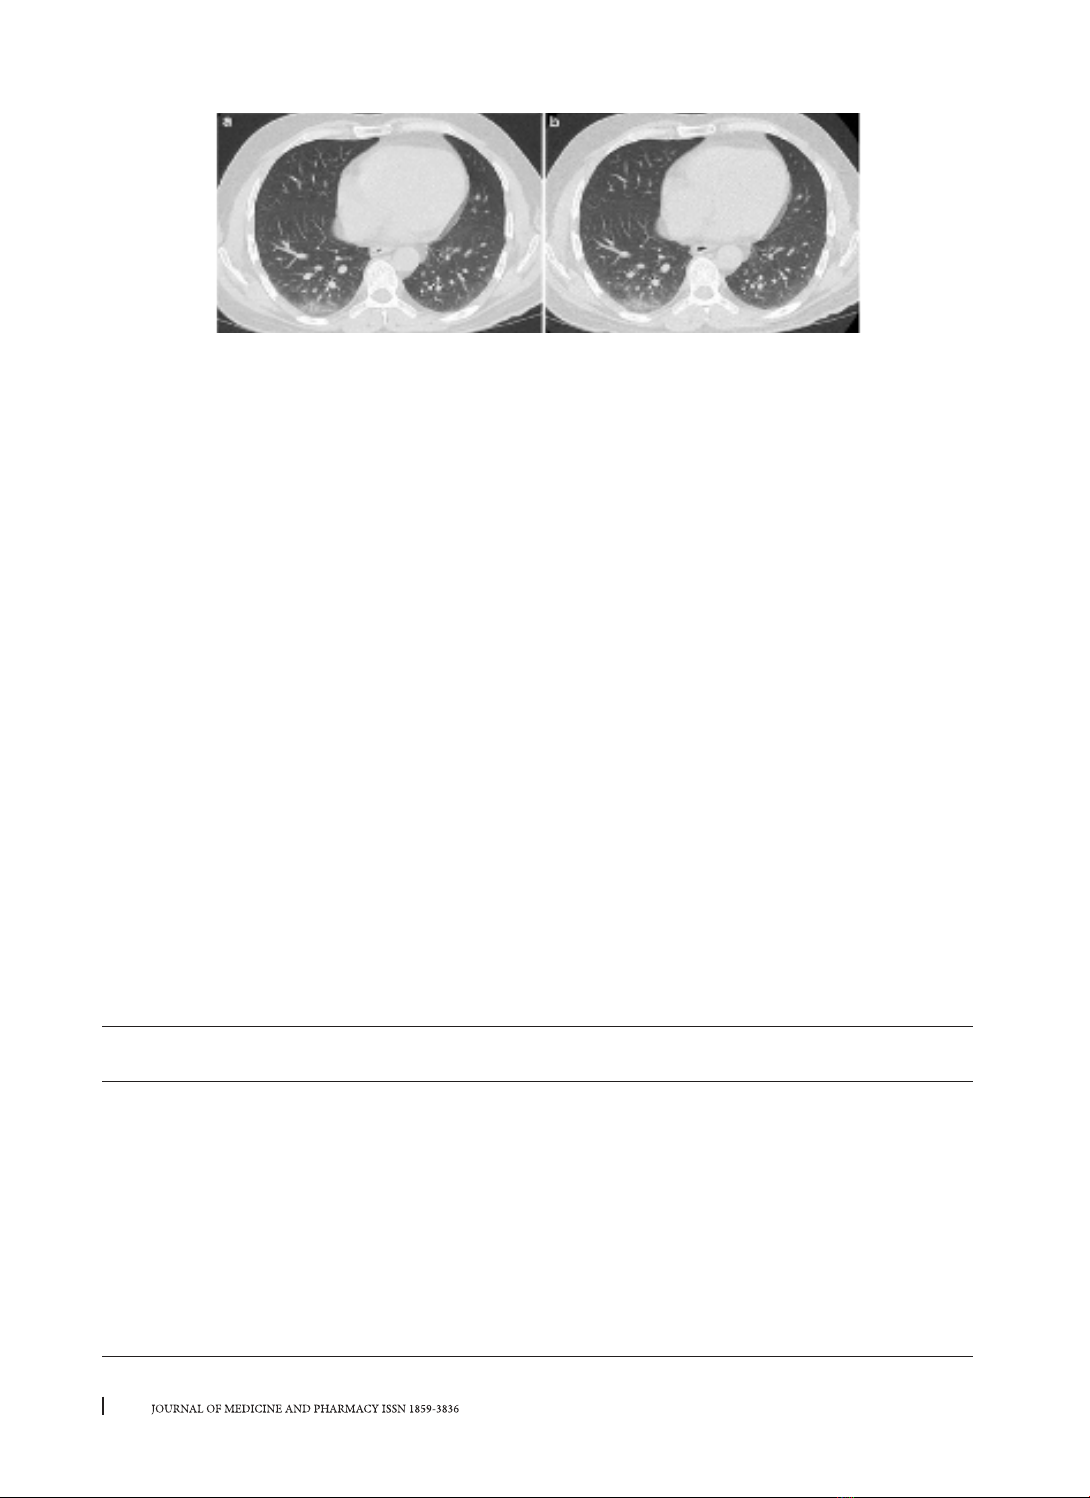

Hình 3. CLVT Phổi ở bệnh nhân viêm phổi do Covid-19 có hình ảnh kính mờ ở phía sau thuỳ dưới phổi phải

trên phim liều tiêu chuẩn (a), hình ảnh tương tự được thấy rõ ràng trên phim liều thấp (b) [15].